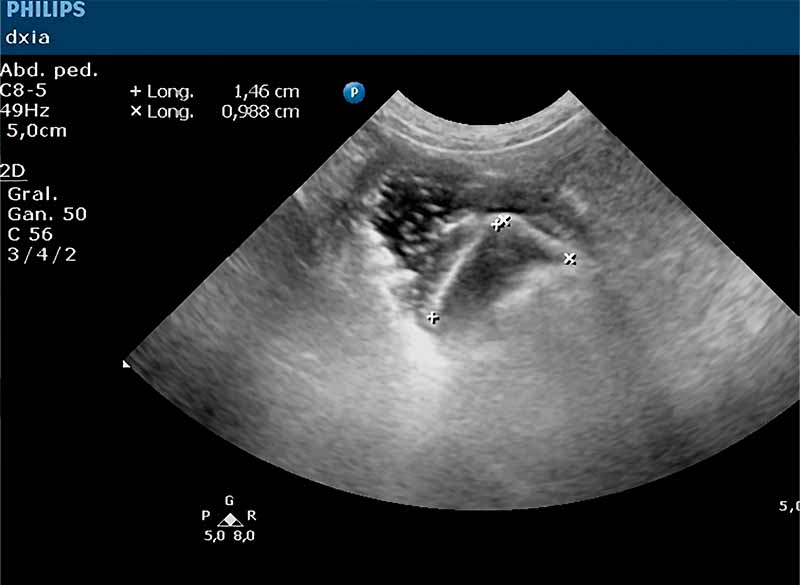

Hallazgos Ecográficos:

Estructura linear hiperecogénica con sombra acústica posterior de morfología punzante, provocando distensión del segmento correspondiente del intestino delgado.

Confirmación quirúrgica de cuerpo extraño (piedra). Resolución del cuadro clínico tras la extracción.